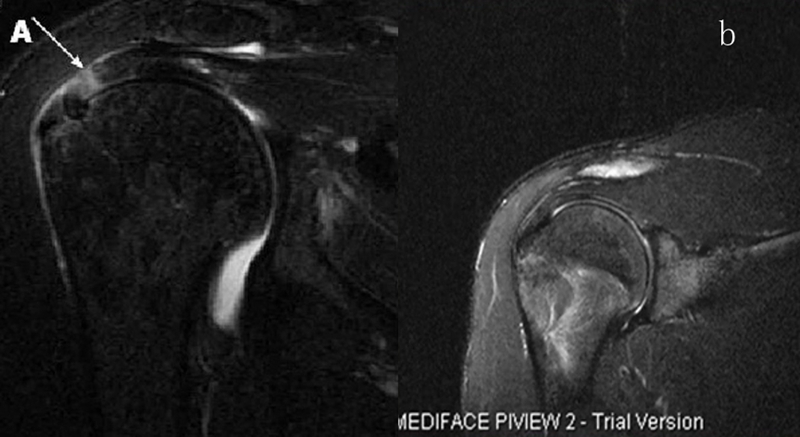

2、MRI检查

MRI目前是诊断肩袖疾病中最常用的检查,可以直观的观察肩袖肌腱。

图24 a.肩袖全层撕裂;b.正常MRI

图25 巨大肩袖损伤(冈上肌)